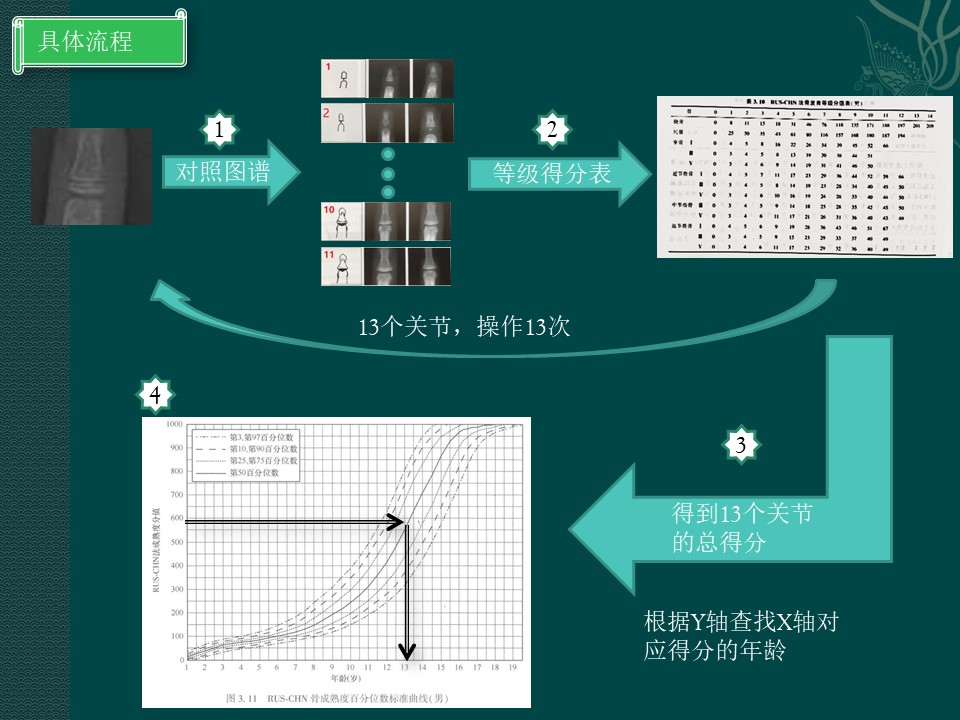

骨龄和RUS-CHN计分法

这个放射临床骨龄工作,可以看出是一项耗精力耗时间的工作。

需要对照13个关节的图谱才能计算骨龄